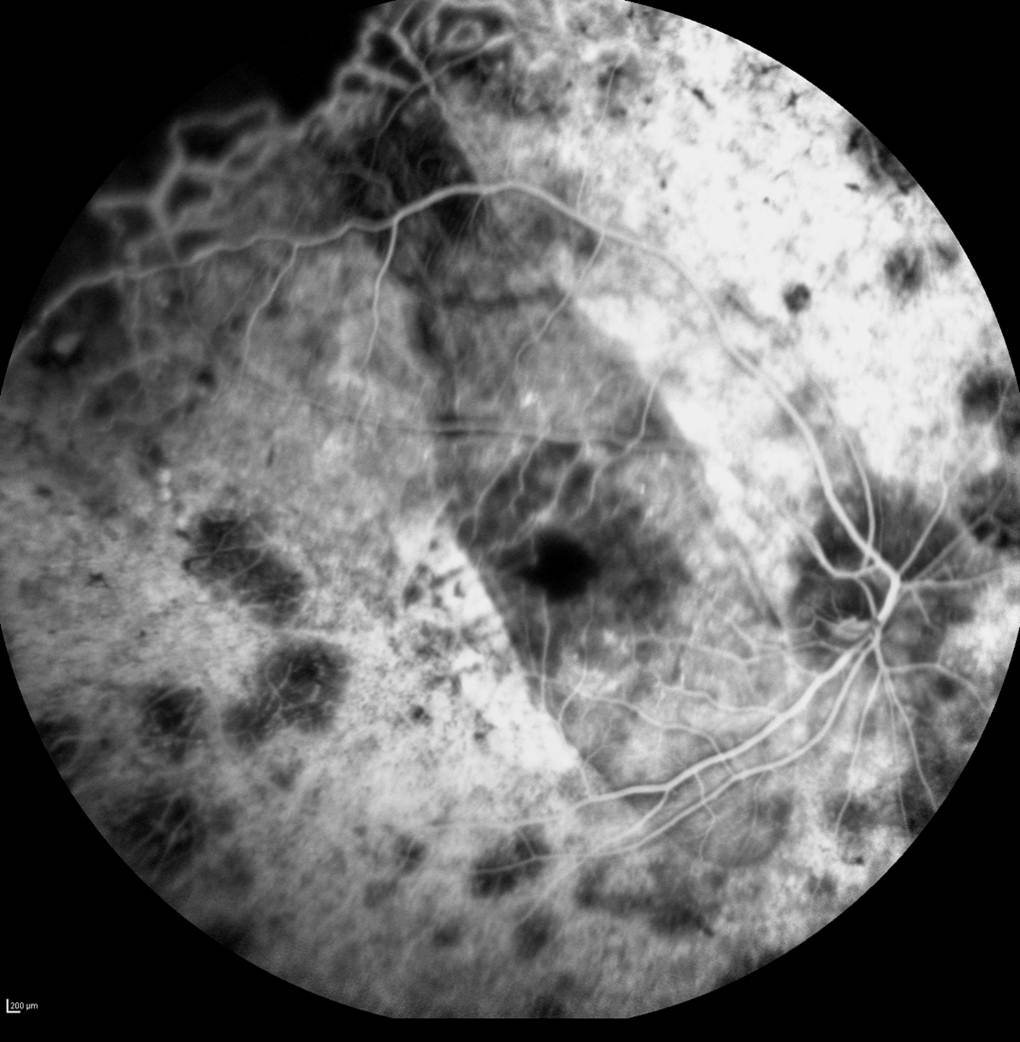

人工視網膜佈有1500個電極,進行植入手術時,需要將晶片植入視網膜下,特別是黃斑區域。這人工視網膜早前於德國進行的首次人體臨床試驗,結果已刊登於業界評審期刊《Proceedings of the Royal Society B》中。臨床試驗結果指出將晶片植入視網膜下的黄斑區域,可產生最佳效果,讓病人能辨認周邊物件及閱讀文字。